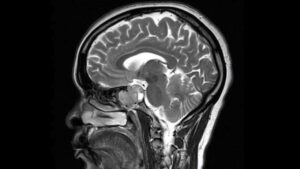

Гипофизом называется придаток мозга, который имеет округлый вид. Он является и органом внутренней секреции, вырабатывающим гормоны, влияющие на рост, обмен веществ и функцию репродукции индивидуума. Гипофиз становится основной частью эндокринной системы человека. Но также эта железа с большим функционалом занимает одно из первых мест по образованию на ней опухолевых проявлений. Так аденома гипофиза мрт которой становится сверхнеобходимой частью диагностических мероприятий, достаточно опасное заболевание. Но только благодаря такимисследованиям врач сможет подобрать необходимое лечение, которое принесет положительный эффект. Клиническая картина подскажет медику, что стоит назначить МРТ или КТ этой железы. Разницу между этими методами можно объяснить принципами действия, и ограниченностью одного из них. КТ нельзя делать более чем один раз в течение года. А МРТ не подойдет маленькому ребенку, поскольку в процессе проведения процедуры нельзя двигаться, а приковать его к одному месту попросту невыполнимо.

Однако если медик заговорил о проведении МРТ головного мозга и гипофиза, то не нужно забывать про эту процедуру. Сделанная вовремя процедура и правильный диагноз позволяет осуществлять эффективное лечение и порой даже не просто вылечить, а и подарить жизнь человеку. Каждая шестая опухоль этого сложного органа представляет собой аденому гипофизу. Такой опухолевый процесс образуется на железистых тканях гипофиза. Образоваться и развиваться опухоль способна в бессимптомном режиме. При ее обнаружении излечение медикаментами уже не в состоянии помочь пациенту. Первые подозрения на возникновение аденомы гипофиза должны стать направлением пациента на магнитно-резонансную томографию гипофиза.

Показания для проведения МРТ гипофиза, следующие: черепно-мозговые травмы, регулярные боли в области головы, скачок и понижение зрения, сокращение области периферийного зрения, неполадки в функционировании остальных желез организма, гормональные изменения, нарушение репродуктивной функции женского организма, нарушение эректильной дисфункции в мужском организме, подозрение на карликовость или гигантизм, сильная худоба или ожирение.